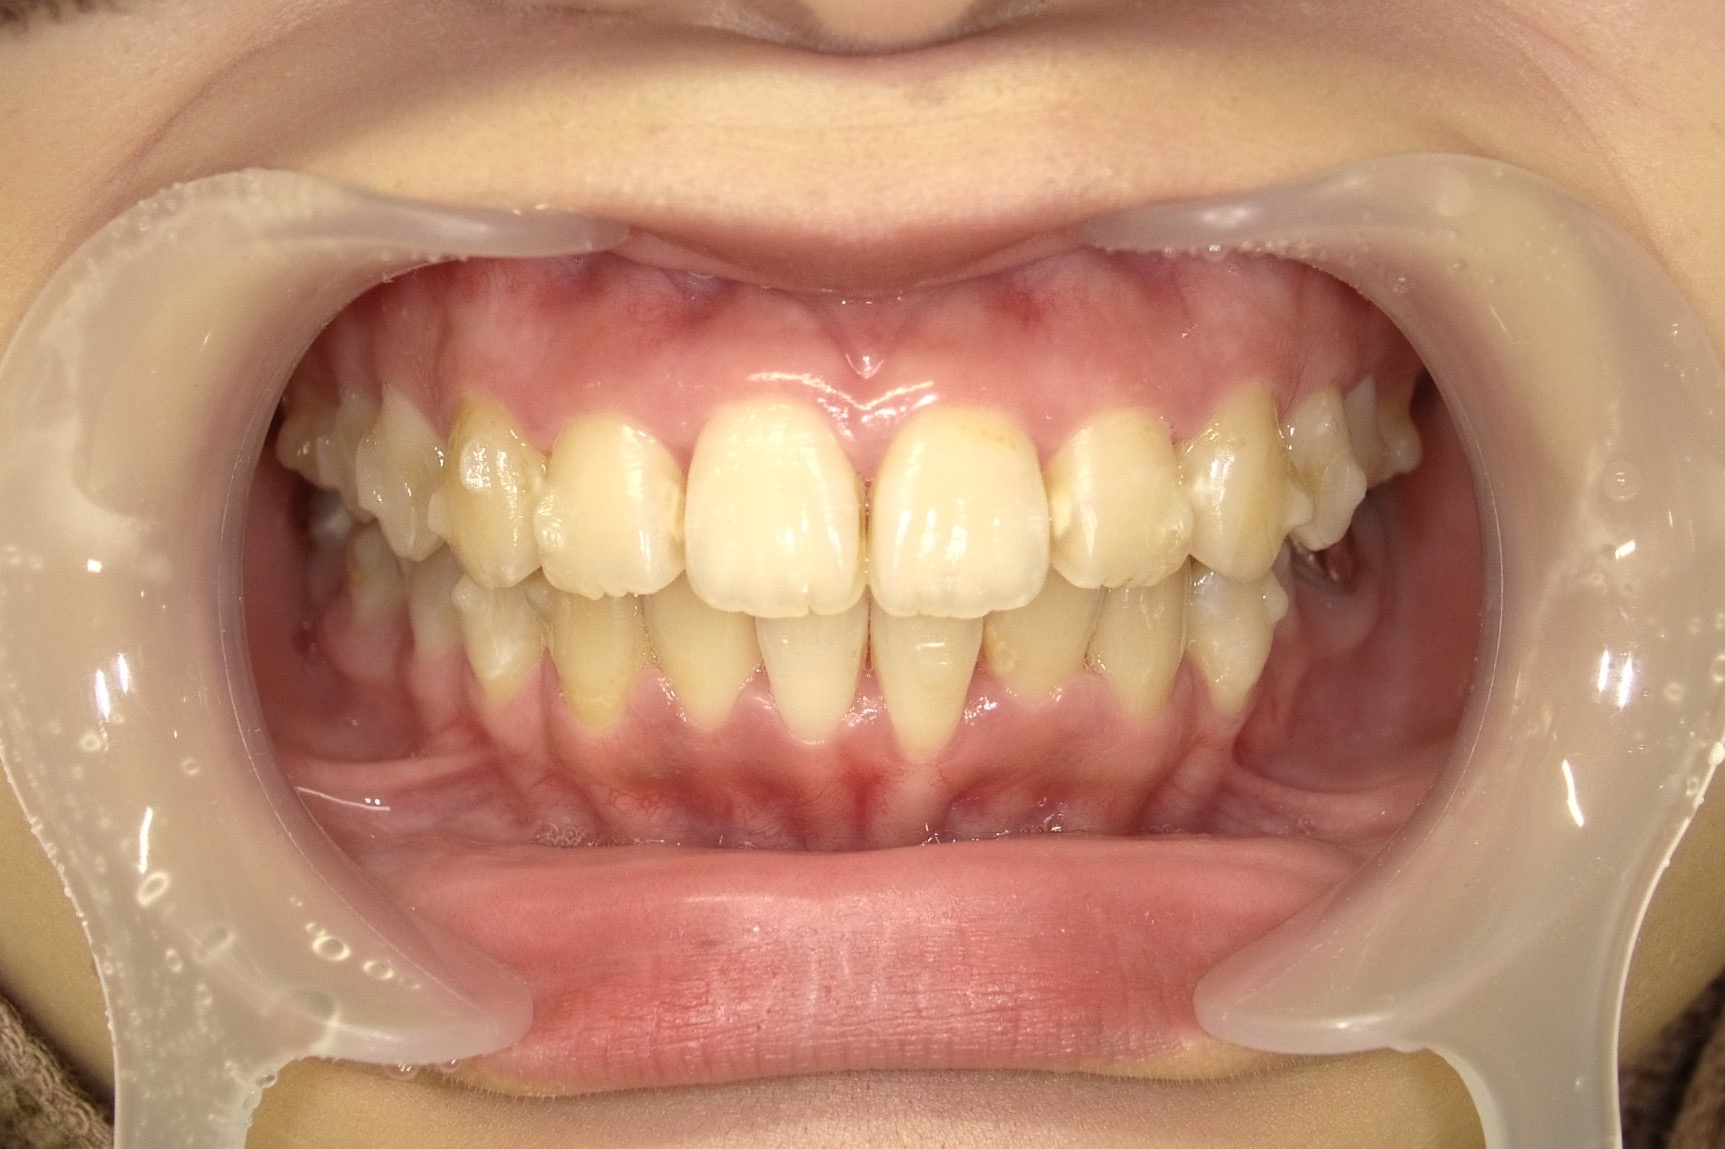

■ 治療後の状態(After)

インビザライン矯正により前歯の傾きが改善され、歯列のアーチが整ったことで出っ歯の印象が軽減しました。

また、下顎の歯の重なりも解消され、歯並び全体がすっきりと整った状態になっています。

■ 治療内容の概要

治療方法:マウスピース型矯正装置(インビザライン)

治療期間:6ヶ月